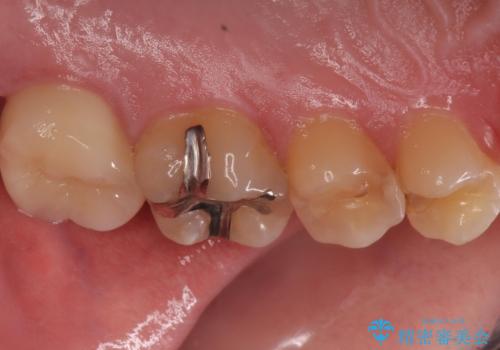

- 左上7 仮歯:11,000円 / ジルコニアクラウン:121,000円 合計132,000円費用は治療当時の料金となります

かなり大きな虫歯でしたが症状も出ず、根管治療もせずに終えることができました。